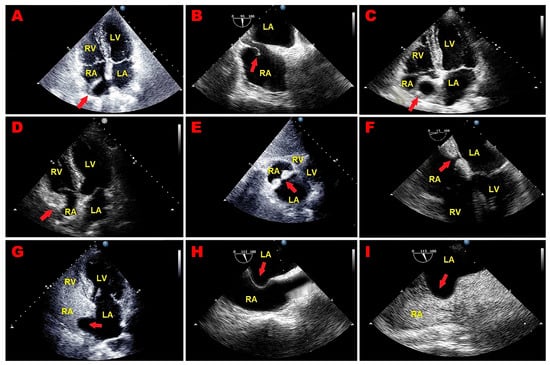

An 84-year-old male (BSA 1.63 m2, BMI 19 Kg/m2) was admitted to the emergency department of our institution due to fever, asthenia, and cough. As per past medical history, the patient was affected by chronic renal failure and ischemic dilated cardiomyopathy with reduced left ventricular ejection fraction (LVEF). He was previously implanted with a bicameral cardioverter–defibrillator. Upon physical examination, blood pressure was 126/79 mmHg, and heart rate was 123 b.p.m., with a body temperature of 38 °C. Arterial blood gas analysis revealed an oxygen saturation of 91%, pH of 7.43, mild hypoxemia (PaO2 = 76 mmHg), and normocapnia (PaCO2 = 35 mmHg). The electrocardiogram (ECG) detected atrial fibrillation (AFib) with left bundle branch block with rapid ventricular rate (Figure 1A). Blood tests showed neutrophilic leukocytosis [white blood cell count 43 × 109/L (range 4–11 × 109/L)], C-reactive protein of 22 mg/dL (range 0.05–0.50 mg/dL), and an estimated glomerular filtration rate of 18.5 mL/min/m2 with markedly elevated levels of D-dimer (>20,000 ng/mL) and N-terminal pro-B-type natriuretic peptide (NT-proBNP) (>10,000 pg/mL). An urgent TTE highlighted a large, S-shaped, and extremely mobile RA mass tethered to Chiari’s network, free-floating and prolapsing through the tricuspid valve into the right ventricle (Figure 1B–D). By placing a 5 mm sample volume of PW-TDI at the level of the mobile portion of the RA mass, a peak antegrade longitudinal velocity of 22.8 cm/s was recorded (Figure 1E). On PW-TDI, the RA mass showed a pattern of incoherent motion, with different velocities and directions compared to the surrounding myocardial tissue. Given the severe renal failure, contrast-enhanced chest CT could not be performed. Chest X-ray showed hilar congestion, multifocal pneumonia, and right pleural effusion (Figure 1F). The patient was hospitalized in the internal medicine ward. He was in poor general condition. Blood cultures and transesophageal echocardiography were not performed, and the patient was conservatively treated with anticoagulants (subcutaneous calcium–heparin 5000 I.U. every 12 h), intravenous (IV) antibiotics (piperacillin plus tazobactam 2.25 g every 8 h), IV diuretics (furosemide 40 mg/die), and beta blockers (metoprolol 150 mg/die). A follow-up TTE was performed after one week, demonstrating the complete resolution of the RA mass (Figure 1G). Accordingly, infective endocarditis was excluded, and the RA mass was judged to be compatible with a thrombus of the RA cavity entrapped within the Chiari network, which was promptly resolved through the use of antithrombotics. Despite the intense cardio-protective treatment, the patient’s condition quickly worsened, resulting in septic shock and death after two weeks of hospitalization.

Figure 1.

(A) Twelve-lead electrocardiogram, showing atrial fibrillation with left bundle branch block and rapid ventricular rate. (B) Transthoracic echocardiography. Apical four-chamber view, demonstrating a large, S-shaped thrombotic mass (red arrow) occupying the whole right atrial cavity. (C) Transthoracic echocardiography. Right ventricular focused apical four-chamber view showing the right atrial thrombotic mass (red arrow) between the Chiari network and the right ventricular lead. (D) Transthoracic echocardiography. Right ventricular focused apical four-chamber view showing the S-shaped right atrial thrombus tethered to Chiari’s network (red arrow), free-floating and prolapsing through the tricuspid valve into the right ventricle. (E) Pulsed wave tissue Doppler imaging is used to assess the right atrial mass mobility. Its motion was very rapid and uncoordinated, with increased peak antegrade velocity, measured by positioning the sample volume of pulsed wave tissue Doppler imaging on the free mobile portion of the mass. (F) Chest X-rays. Posteroanterior view showing hilar congestion, multifocal pneumonia, and right pleural effusion. (G) Transthoracic echocardiography. Right ventricular focused apical four-chamber view, revealing the complete disappearance of right atrial thrombotic mass. LA, left atrium; LV, left ventricle; RA, right atrium; RV, right ventricle; Va, antegrade velocity.